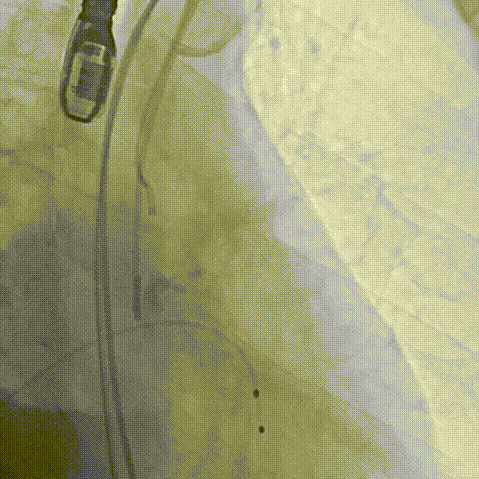

周达新教授 复旦大学附属中山医院 共识引路,干瓣启新,共赴临床解决方案:当前,结构性心脏病的介入治疗已迈入微创化、精准化的新时代。技术的革新、创新器械的上市,都是我们中国技术领跑的印证,《专家共识》的应运而生是中国医生对于行业“规范化”的践行,让治疗更精准、让医者更贴近“以患者为中心”的医疗本质。 潘文志教授 复旦大学附属中山医院 严谨求真重思考 创新临床互验证:在医学的漫长征途中,新器械的突破与严谨的临床研究是两大核心驱动力。拥抱创新的同时需要严谨求证,预装干瓣作为创新器械,其即取即用的特性可以很好的适配“急诊”的场景,此外,国产创新不是简单的复制,干瓣的瓣叶质地不是字面意思“干”的,而具“曲柔性”。所以,需要多看多测,才能全面了解一款产品。《经导管心脏瓣膜治疗术》的问世也是凝结着我们带着临床思维思考的结晶的“独家秘笈”,希望能够将“来时的路”变成未来行业同行者的“高效学习之路”! 患者病史 多病共存陷困境,主动脉瓣狭窄成 “首要威胁” 现病史:患者反复活动后胸闷2年余,无胸痛、心悸,无头晕、晕厥等不适,未予重视。患者轻微体力活动(快走、爬楼梯)即胸闷气促,静息及夜间无不适,无咳嗽、心悸等症状。为进一步诊疗收入我科,患病以来精神、食欲、睡眠、二便及体重均正常。 既往史: 2025年5月7日因小便不畅至外院住院病理穿刺确诊前列腺癌,期间检查心超提示主动脉瓣钙化伴重度狭窄,遂暂缓前列腺手术。2025年05月30日至我院就诊。 2025年5月20日开始服用比卡鲁胺片。患者血脂异常,长期服用丹参滴丸,麝香保心丸,心通颗拉。 手术史外伤史:10年前行肺手术,具体不详。否认外伤史。 入院检查 心电图提示:窦性心动过缓;ST-T改变; 心超显示:主动脉瓣钙化伴重度狭窄及轻度反流,Vmax 4.8m/s、PGmax 93mmHg、PGmean 47mmHg;左房增大,左室壁增厚。 冠状动脉CT造影:左前降支中段浅表心肌桥,主动脉瓣增厚伴重度钙化,主动脉粥样硬化。 术前CT 三叶瓣,中度钙化,主动脉根部直径25.4mm,LVOT直径23.5mm 双侧冠脉开口高度尚可,瓦氏窦尚可,ST尚可,升主尚可,冠脉风险小;中度钙化,心脏角度39.2°;心腔内径可,左室壁增厚。 外周走行尚可,全主动脉存在散在钙化,右侧穿刺点需避开钙化,血管内径可,血管内壁存在纤维增厚。 手术策略:右侧股动脉为主入路,使用20F大鞘;20球囊预扩,植入AV29瓣膜; 手术过程 主动脉根部造影 输送系统柔顺过弓 定位 缓慢释放瓣膜 造影观察 稳定脱钩 最终造影性钙位置良好,轻微瓣周漏 术后超声:轻度瓣周漏,术后平均压差11mmHg 出院前超声:平均压差11mmHg 在多基础疾病患者日益增多的当下,该病例也为临床提供重要启示:针对合并肿瘤、既往手术史的复杂瓣膜病患者,需通过多学科协作(心内科、肿瘤科、麻醉科等)全面评估病情,结合精准影像技术与适配器械,制定个体化手术方案,才能在保障安全的同时,实现最优疗效。 作为中国结构性心脏病领域的标杆学术活动,中国结构周 2025为这类高水平临床病例提供了交流平台,助力推动我国结构性心脏病诊疗技术持续创新,让更多复杂瓣膜病患者受益于精准医疗方案。 ProStyle A®预装干瓣——助力临床最优化解决方案: 轻松过弓,精准可控:该病例全主动脉存在散在钙化,右侧穿刺点需避开钙化,ProStyle A®较细的尺寸+柔顺的输送系统通过性能得到了很好的验证; 平稳释放:平衡的径向支撑力降低了释放过程中的张力,流入端小锥角设计能够迅速锚定贴边; 预装干瓣 便捷顺安:金仕生物专利抗钙化技术运用纳米技术去除组织内的细胞碎片和磷脂,封闭游离醛基,从根本上阻断了瓣膜钙化的多项因素,显著提升了瓣膜的耐久性;同时,相比较传统戊二醛保存方式,干式存储最大限度的保留心包的亲水亲油平衡,还原组织天然曲柔性,进一步保障了瓣叶开合,保证长期耐久性; 专家简介 葛均波 复旦大学附属中山医院(点击查看专家详细简历) 周达新 复旦大学附属中山医院(点击查看专家详细简历) 潘文志 复旦大学附属中山医院(点击查看专家详细简历) · END ·